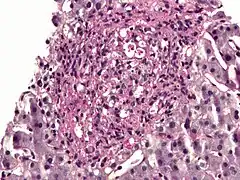

Histopathology of Histoplasma capsulatum, GMS stain, showing narrow budding yeast

The budding yeast cells formed in infected tissues are small (about 2–4 µm) and are characteristically seen forming in clusters within phagocytic cells, including histiocytes and other macrophages, as well as monocytes. An African phylogenetic species, H. duboisii, often forms larger yeast cells to 15 µm.